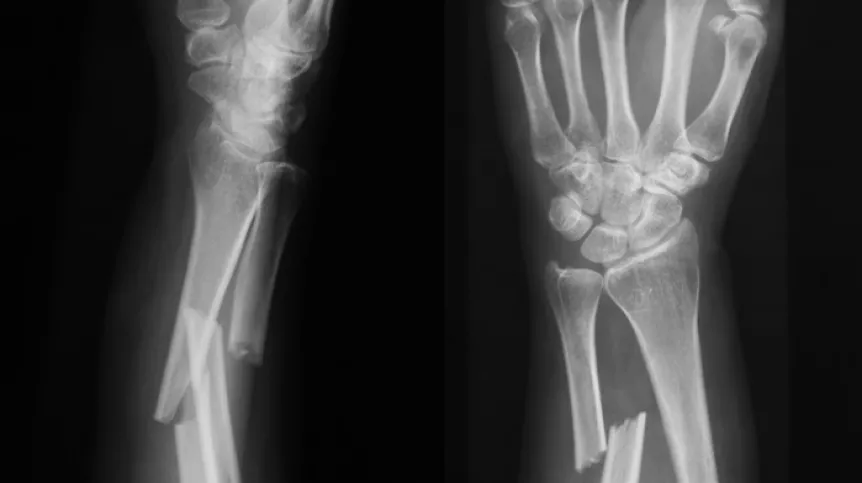

Jak podkreśla lider, obecne metody leczenia złamań są kosztowne i czasochłonne. W najtrudniejszych przypadkach przy opóźnionym zrastaniu się stosuje się m.in. przeszczepy kości, wszczepienia rusztowań, a także wstrzykuje się substancje stymulujące wzrost tkanki kostnej. Te procedury często wymagają operacji chirurgicznej, co niesie ze sobą ryzyko powikłań, takich jak krwawienie czy zakażenie.

Materiał ma spełniać potrzeby osób, których kości goją się zbyt wolno lub w ogóle się nie zrastają. Problemy z opóźnionym zrastaniem się kości dotykają 5-10 proc. osób z urazami, zwłaszcza przy złamaniach kości udowej i piszczelowej w wyniku wypadków np. samochodowych. Wiek pacjenta wiąże się z ryzykiem - im starszy pacjent, tym większe ryzyko powikłań przy leczeniu złamań, zwłaszcza u osób z osteoporozą. Wśród młodszych pacjentów złamania kości najczęściej wynikają z urazów takich jak kontuzje sportowe, upadki z wysokości, oraz coraz bardziej problematyczne dla systemów opieki zdrowotnej na całym świecie – wypadki komunikacyjne.